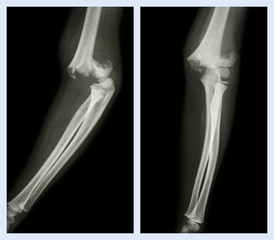

Podobny obraz Medical Elbow Anterior View X-Ray Radiograph Illustrating...